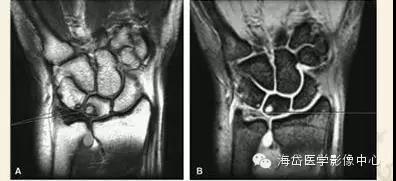

②MRI:MRI对骨髓变化敏感,在骨损伤早期就能反映出骨髓水肿性改变,可做到早期诊断。

随压迫时间延长MRI可见高信号(T2WI)逐渐增强,并形成透镜样改变,晚期形成“双线”或“双环”征。“双环”征提示坏死区内可能有新骨形成,“双线”征表明骨坏死区有瘢痕组织形成。

由于尺骨阴性、阳性变异引起的骨坏死是可逆的,当尺骨变异被纠正后骨坏死可以转化为正常骨结构。因此MRI除可用于早期诊断外还可作为有效的动态观察手段,当骨髓水肿性变化无减轻、消失,反而逐渐明显时,提示临床应早期解除桥联状态(主要是解除压迫),可有效防止月骨、三角骨坏死的发生或降低其发生率。